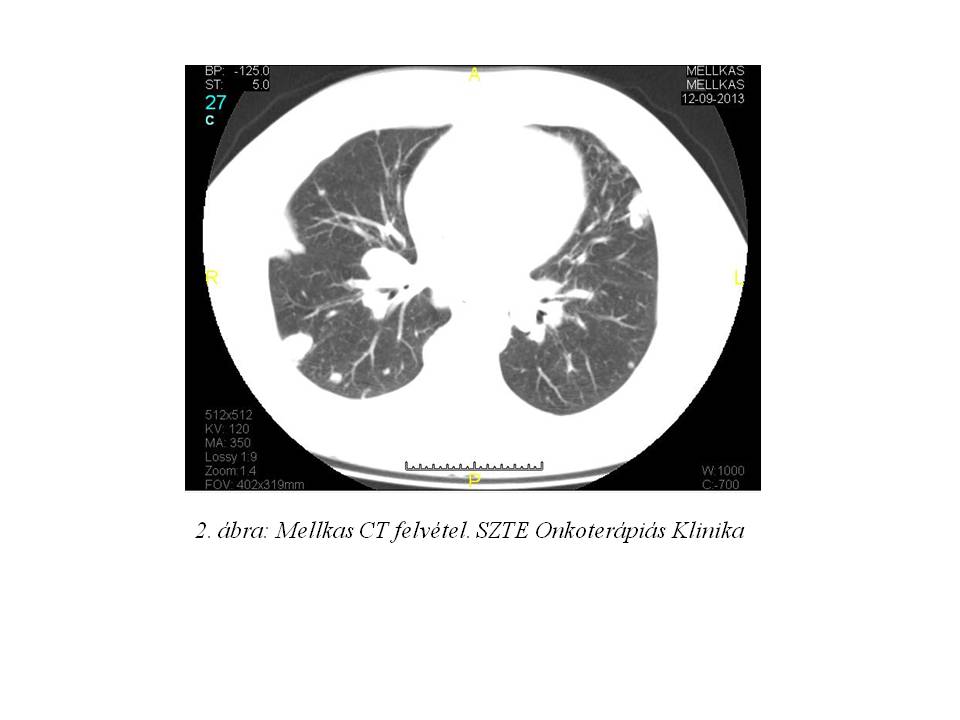

A staging vizsgálatok részeként készült mellkas CT-n szeptemberben a tüdőkben elszórtan, számos 23 mm körüli és ennél kisebb, helyenként összefolyó jellegű nodulus ábrázolódott. A hilusokban és a mediastinumban néhány 22 mm nagyságú nyirokcsomó volt látható (2. ábra).